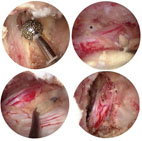

本院骨科部自2005年起就專注於脊椎微創手術的研究和治療,2018年起更領先全國各大醫療院所開發創新的「雙通道脊椎微創內視鏡手術技術」英文名為 Unilateral Biportal Endoscopic (UBE) Surgical Technique。手術時我們透過一個約半公分大小的通道來灌注生理食鹽水及置入高解析內視鏡;另一個約1公分大小的通道,則用來引流生理食鹽水及操作各種手術器械(如圖一)。生理食鹽水的靜水壓和高解析度內視鏡,讓骨科醫師可以在高倍放大、清晰、乾淨而且不會流血的小小的手術空間裡進行精細的手術,視野裡乾淨透亮的程度有如在潛水時欣賞美麗的海底世界一樣(如圖二),大幅降低手術中神經組織受傷的風險。

圖一、A.UBE手術技術示意圖;B. UBE手術情景;C. UBE手術的兩個小傷口;D.高解析度內視鏡清楚明亮的影像